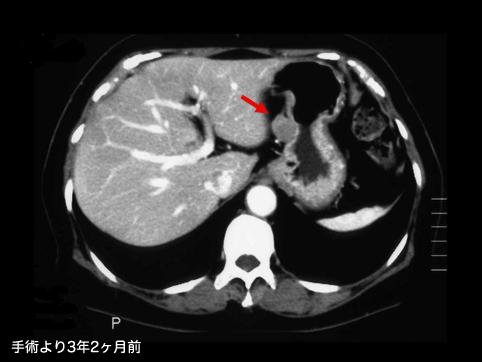

A case of gastrointestinal stromal tumor that extraluminally developed in size during four years and ten months.

Malignant non-epithelilal tumors/Leiomyosarcoma (including GIST)

Stomach/Body

CT

10 - 14